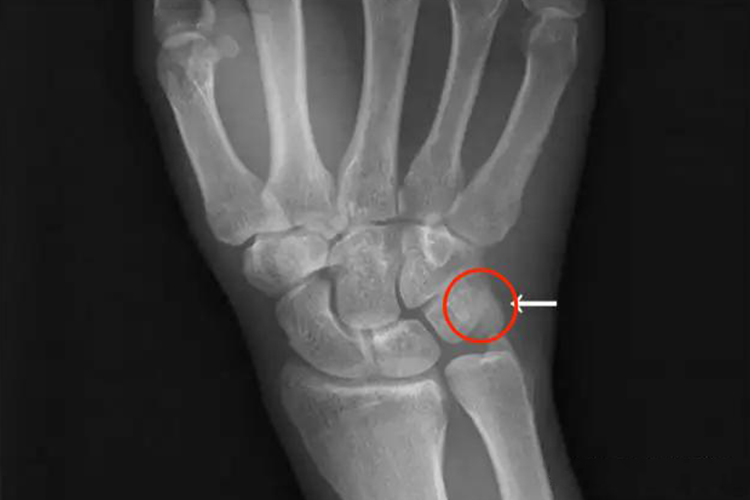

手腕豆状骨的形状像一颗豆子,疏松地与三角骨的掌面联结。

手腕豆状骨的形状像一颗豆子,疏松地与三角骨的掌面联结。豆状骨容易移动也容易触诊,它被镶嵌于尺侧腕屈肌的肌腱,具有种籽骨的特征。